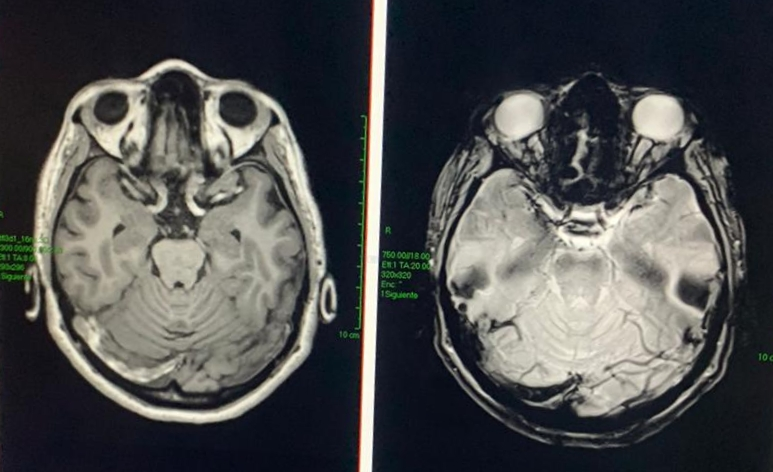

5/ as an example, today we attend a 44 year old woman, abandoned by her husband with three children in the middle of the #pandemic, who had an acute onset of affective and cognitive abnormalities, hallucinations and catatonia. MRI shows a cerebral venous trombosis.